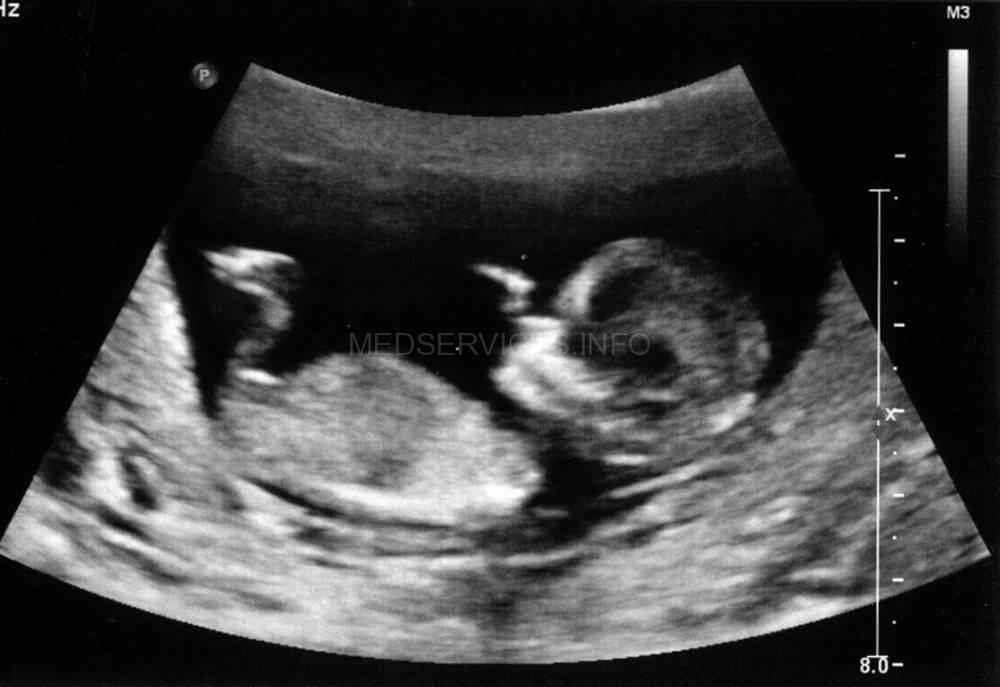

При эхографии в 37 нед беременности на фоне многоводия был обнаружен один живой плод мужского пола с аномальным внешним видом. Все длинные трубчатые кости были укорочены и соответствовали 26 нед гестации (рис. 1).

Рис. 1. Укорочение костей голени (микромелия).

Грудная клетка была гипоплазирована. Ее размеры резко диссоциировали с размерами живота плода (рис. 2, 3).